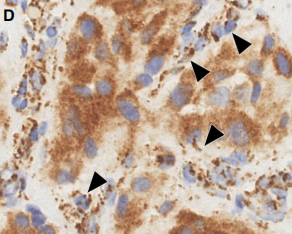

- SDHB标记: SDHA/B/C/D/AF2基因(统称SDHx)的突变或甲基化均可导致SDHB蛋白表达异常(缺失或减弱)。SDHB表达异常提示可能存在SDH缺陷相关的遗传性肿瘤综合征。本例患者SDHB蛋白表达正常。

SDHB免疫组化结果判读示例:A图为正常表达(胞浆颗粒状强阳性),B-F图均为不同模式的表达异常 [引自PMID:35546442]